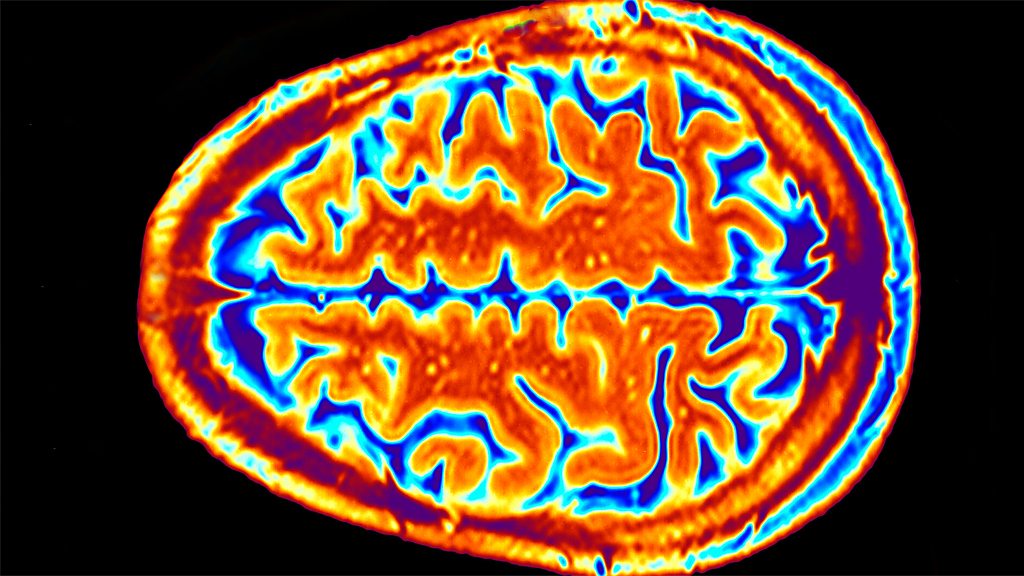

For the regular feature Show Us Your Instrument, Inside Science meets the MRI machine. Professor Sophie Scott, cognitive neuroscientist at University College London, explains how the scanners use quantum physics to disrupt protons inside your body, and why you should try and avoid pressing the emergency 'quench' button unless you're willing to destroy the laboratory.